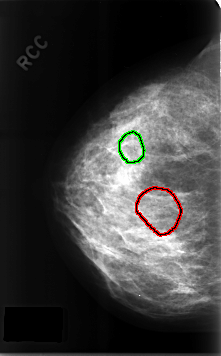

C_0309_1.RIGHT_CC

FILE: C_0309_1.RIGHT_CC.OVERLAY

TOTAL_ABNORMALITIES 2

ABNORMALITY 1

LESION_TYPE CALCIFICATION TYPE PLEOMORPHIC DISTRIBUTION CLUSTERED

ASSESSMENT 5

SUBTLETY 4

PATHOLOGY MALIGNANT

TOTAL_OUTLINES 1

BOUNDARY

ABNORMALITY 2

LESION_TYPE CALCIFICATION TYPE AMORPHOUS DISTRIBUTION CLUSTERED

ASSESSMENT 4

SUBTLETY 3

PATHOLOGY BENIGN